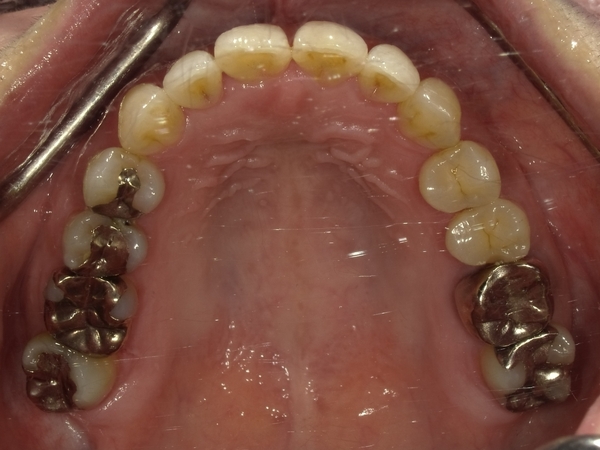

ガタガタとした歯並びや八重歯(叢生)CASE71